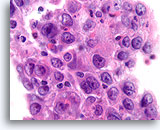

Atypische ductale hyperplasie, Borst FNA, Celblok.

Dit plaatje van de naaldspoeling van de patiënt in afbeelding 15 toont een uniforme populatie van vrijelijk stratificerende ductale cellen met een uniforme spreiding van kernen, afwezigheid van een stromingspatroon en de aanwezigheid van uniformere ronde ruimten in het kleinere fragment.

Atypische ductale hyperplasie, Borst FNA, Celblok.

Dit plaatje van de naaldspoeling van de patiënt in afbeelding 15 toont een uniforme populatie van vrijelijk stratificerende ductale cellen met een uniforme spreiding van kernen, afwezigheid van een stromingspatroon en de aanwezigheid van uniformere ronde ruimten in het kleinere fragment.

Atypische ductale hyperplasie, Borst FNA, Celblok.

Let op de gelijkvormigheid van de cellen (dit duidt op een afwezigheid van myoepitheliale cellen) en de uniforme spreiding van cellen zonder gedeelde polariteit.

Atypische ductale hyperplasie, Borst FNA, Celblok.

Let op de gelijkvormigheid van de cellen (dit duidt op een afwezigheid van myoepitheliale cellen) en de uniforme spreiding van cellen zonder gedeelde polariteit.